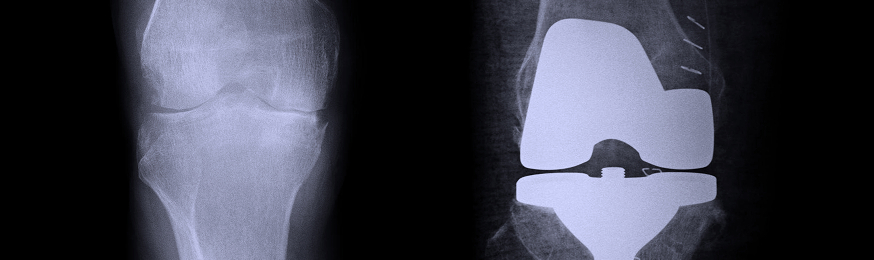

This device is made by DePuy Orthopaedics, Inc., a subsidiary of Johnson & Johnson. It is used in reconstructive knee surgery.

The FDA says it issued the recall notice due to the possibility that the device’s sleeve-to-sleeve base taper connection may not be able to accommodate potential physiologic loads during normal movement by some patients. As a result, the sleeve may fracture at the taper joint, possibly leading to loss of function, loss of limb, infection, compromised soft tissue or death.